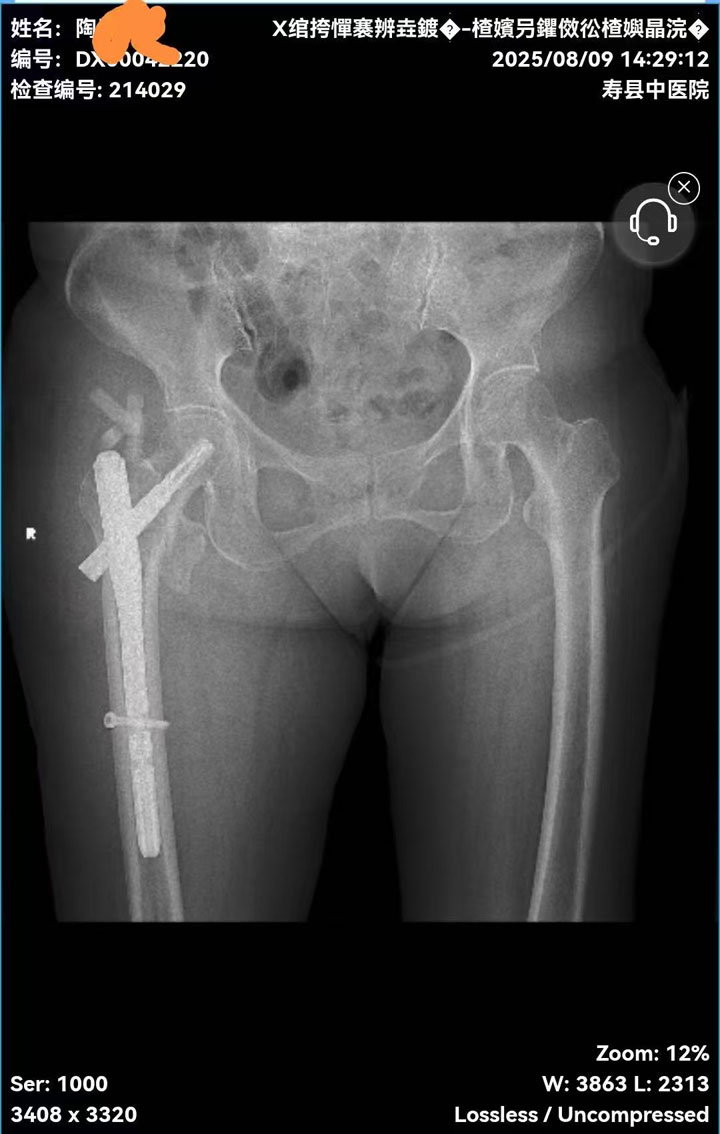

术后固定效果满意

患者陶某某因在家中不慎跌倒导致右股骨粗隆间骨折,被紧急送至我院。髋部骨折被称为“人生最后一次骨折”,高龄患者常合并心肺功能减退、骨质疏松等基础疾病,传统手术风险极高,而PFNA技术凭借创伤小、固定牢、恢复快的特点,成为此类患者的首选治疗方案。

面对患者超高龄、中度贫血及慢性支气管炎等复杂合并症,骨科联合麻醉科、内科开展多学科会诊(MDT),量身定制手术方案。手术仅耗时40分钟,出血量不足50ml,最大限度降低了手术风险。